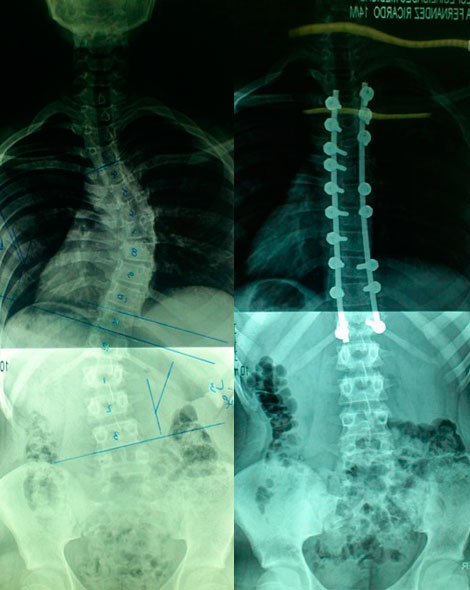

CIRUGIA:

¿Cuándo puede recomendarse la cirugía?

Esto depende:

Curvas mayores de 40 – 45 grados incluso si no han finalizado el crecimiento.

Cuando se alcanza madurez osea, algunas curvas entre 40 y 50 grados progresan y otras no.

Curvas mayores de 50 anos a pesar de ser adultos tienen elevado riesgo de seguir progresando a un ritmo lento.

¿En que consiste la cirugía?